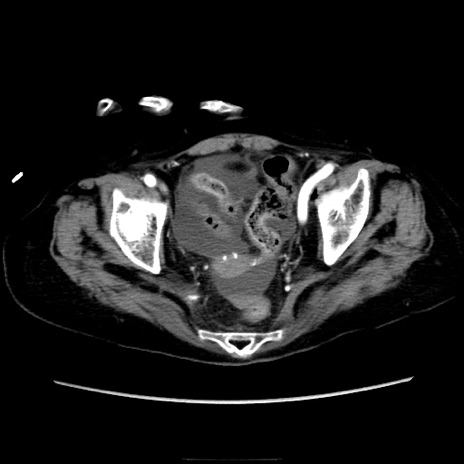

症例40(横断像)

【症例】90歳代女性

【主訴】腹痛・嘔吐

【現病歴】 食欲低下、嘔吐があり昨日他院受診。肺炎と診断され入院となる。入院後より腹部全体に圧痛あり。胃管留置され経過みていたが、症状持続するため、

当院転院となる。

【身体所見】腹部:中央に激痛あり、圧痛あり、反跳痛不明

【データ】WBC 17100、CRP 18.82

横断像